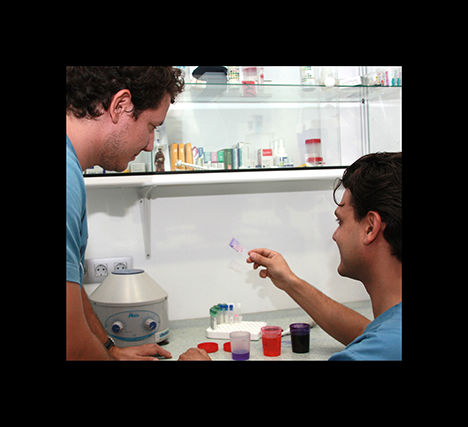

análisis clínicos

En clinican contamos con un laboratorio donde podemos realizar análisis de sangre, orina…